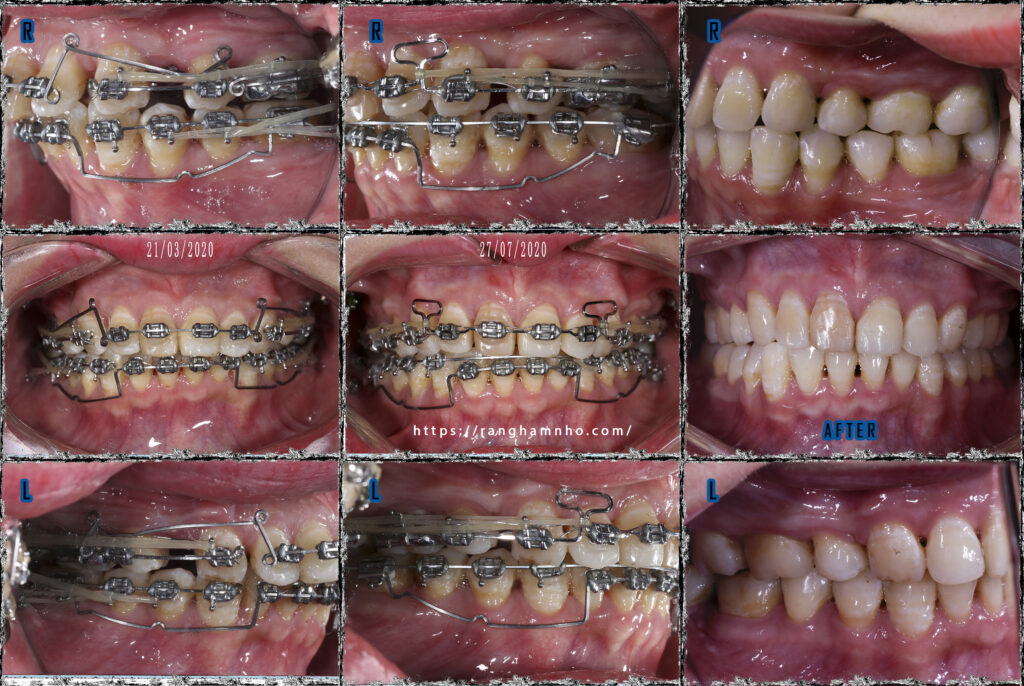

Đóng khoảng, dựng trục, chỉnh khớp cắn và kết thúc sớm cho BN. Tình trạng khớp cắn đã tương đối ổn định, nhóm rằng hàm tiếp khớp tốt. Bệnh nhân ăn nhai tốt, các khoảng đã đóng kín, thẩm mỹ khuôn miệng cười cải thiện nhiều sau điều trị.

Kết quả dựng trục R8 hai hàm đạt thành công khá tốt, tuy nhiên diện tiếp xúc tiếp điểm giữa hai hàm là không được tối ưu, lỗi do chỉ định nhổ răng sai của bác sĩ điều trị trước.